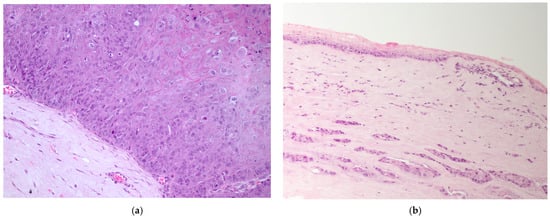

The majority of epithelial neoplasia were SCC (38/41), 2/41 were papillomas, one of which had focal transformation into in situ SCC. All c-SCC and papillomas grew in the central cornea, variably extending to the limbus (Figure 1a,b), except one papilloma with histopathological signs of viral infection, which primarily arose on the limbus (Figure 2a).

Figure 1.

(a) Dog, eye globe, macroscopic picture of cross-section: a large exophytic c-SCC affects the entire surface of the cornea, extending focally to the limbus; (b) dog, eye globe: histological subgross view of a typical exophytic c-SCC, not infiltrating the deeper corneal stroma (EE, 4×).

Figure 2.

(a) Dog, corneal biopsy: corneo-limbal papilloma with scattered koilocytes, suggesting a viral origin (EE, 10×); (b) dog, corneal biopsy: neoplastic cells grow into the corneal stroma apparently without connection with the surface epithelium (stromal invasive pattern) (EE, 10×).

c-SCCs mostly grew as exophytic masses with limited infiltration into the corneal stroma (24/38). In only 8/38 cases, infiltrative growth into the stroma was pronounced; of these, 2/8 cases showed a “stromal invasive pattern”, forming islands of neoplastic cells that dissected the corneal stroma, while the overlaying corneal epithelium was apparently unaffected (Figure 2b). Six cases were in situ SCC (6/38). In one case, neoplastic cells were focally arranged in a pseudoacinar pattern.

In the majority of cases, the tumor extended to the limbus (14/19) (Figure 4a), while fewer were limited to the cornea (5/19). Most neoplasms grew infiltrating the stroma (10/19), two of which (2/10) showed a stromal invasive pattern (Figure 4a and Figure 5a). Six SCCs (6/19) were exophytic, and three (3/19) were in situ SCC.

Figure 4.

(a) Horse, formalin-fixed eye globe, gross features of corneo-limbal SCC (courtesy of Dr. Riccardo Stoppini); (b) horse, eye, clinical aspect of a stromal invasive SCC (courtesy of Dr. Samuela Mazzucchelli).

Figure 5.

(a) Horse, cornea: typical features of stromal invasive SCC; neoplastic cells form islands deep in the stroma, without connection with the corneal epithelium (EE, 10×). (b) Horse, limbus: infiltrative corneo-limbal SCC; severe elastosis is recognizable in the conjunctival lamina propria (EE, 4×). Inset: Detail of the conjunctival elastosis (EE, 40×).

The degree of inflammation was equally distributed between moderate and severe (10/19 cases) and mild or absent (9/19 cases). Elastosis of the bulbar conjunctiva (Figure 5b) and acantholytic cells were evident in 9/19 cases.